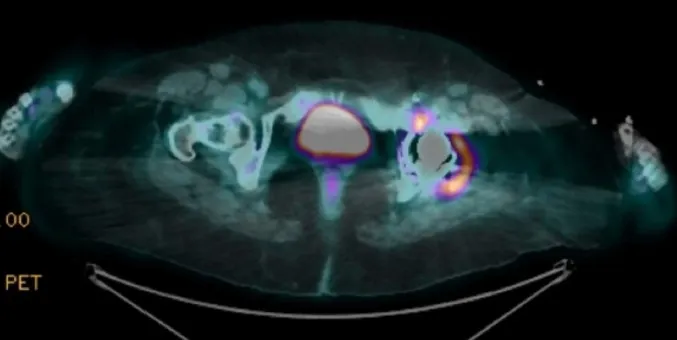

IRA + Icterícia: Um Caso que Exige Investigação Detalhada

IRA + Icterícia: Um Caso que Exige Investigação Detalhada